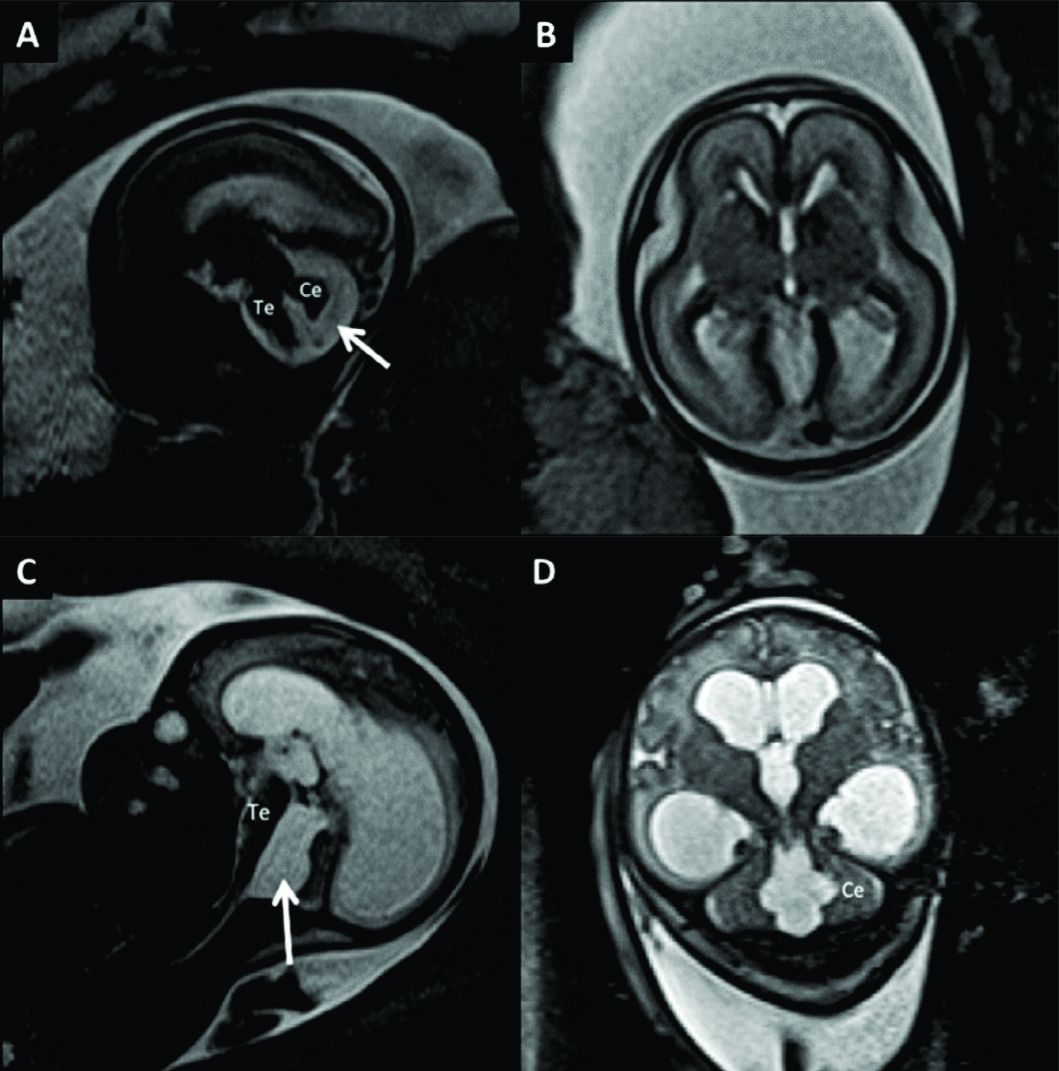

Figura 7

RM Fetal Holoprosencefalia.

RMf a las 28 semanas referido por estudio ecográfico para confirmación de holoprosencefalia. En el plano coronal (A) se identifica la cavidad ventricular única con manto cerebral periférico adelgazado y la característica masa intermedia (MI) por la ausencia de división de ambos tálamos.

En el plano axial (B) los hallazgos son similares con ausencia de estructuras de la línea media como cisura inter-hemisférica u hoz cerebral. Te: Tronco encefálico

Figura 8

RM Fetal Esquizencefalia bilateral.

Estudio de RM realizado en la semana 29 con diagnóstico ecográfico de esquizencefalia bilateral. En el corte axial (A) y coronal (B) se reconocen las clásicas hendiduras que vinculan el sistema ventricular con el espacio sub-aracnoideo de la convexidad en ambos hemisferios.

Las estructuras de línea media son normales así como también el tronco encefálico (Te) y el resto de las estructuras intra-craneanas.